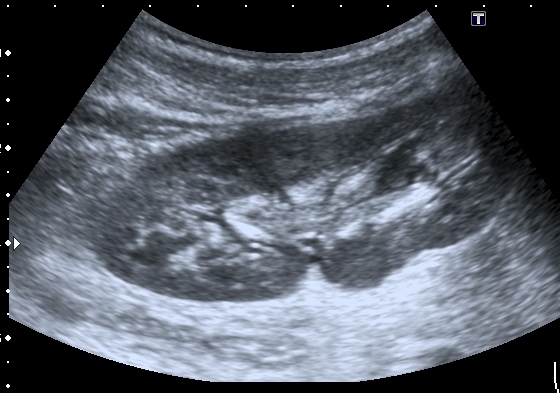

Мальчик 13 лет , страдает гемофилией А. Накануне ударился правым боком , появилась тёмная моча.

На УЗИ - такая картина:

Правая почка - паренхима не изменена, в срединном комплексе - лоханка с толстыми стенками и гиперэхогенным содержимым

Как трактовать данные изменения - Пиелит? Гемапиелос? Отёк стенки лоханки ( по аналогии с желчным пузырём)?

Поэтому правильнее отталкиваться от того что мы видим. А видим мы классические признаки, которые встречаем чаще всего при воспалении ЧЛС - признаки пиелита - признаки отека стенок ЧЛС на фоне воспаления. Здесь аналогичная картина, но, вероятнее всего, вызванная травмой - надрыв - разрыв -нарушение целостности стенки ЧЛС - отек - асептическое воспаление.